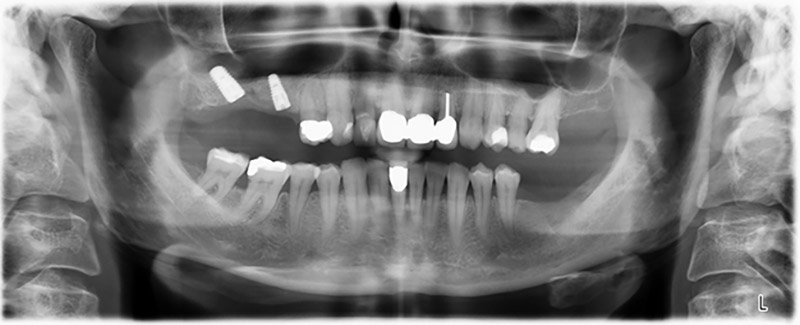

La paziente, 59 anni, presenta un caso di parodontite avanzata e descrive una sensazione di fastidio e scarsa sensibilità gustativa dal primo quadrante in direzione distale. L'esame clinico rivela tasche parodontali generalmente diffuse e un'atrofia ossea molto avanzata nelle regioni 16 e 14. L'esito è confermato dalla radiologia (fig. 1). Non è possibile salvare i denti 16 e 14.